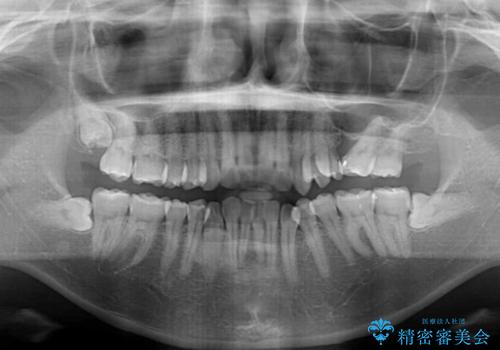

- 全体的なデコボコと、以前抜歯した歯のスペースを閉じた部分が気になるとのことで来院された患者様です。

左上第一大臼歯を抜歯した際に、スペースを閉じたそうですが、歯が傾斜してものが挟まって不快とのことでした。

インビザライン矯正で全体の歯列と整えるとともに、左上第一大臼歯部にはスペースを作り、インプラントによる補綴治療を行うこととしました。

歯の傾斜が改善され、インプラントによるクラウンが装着されたことで、物が挟まることもなくなりました。